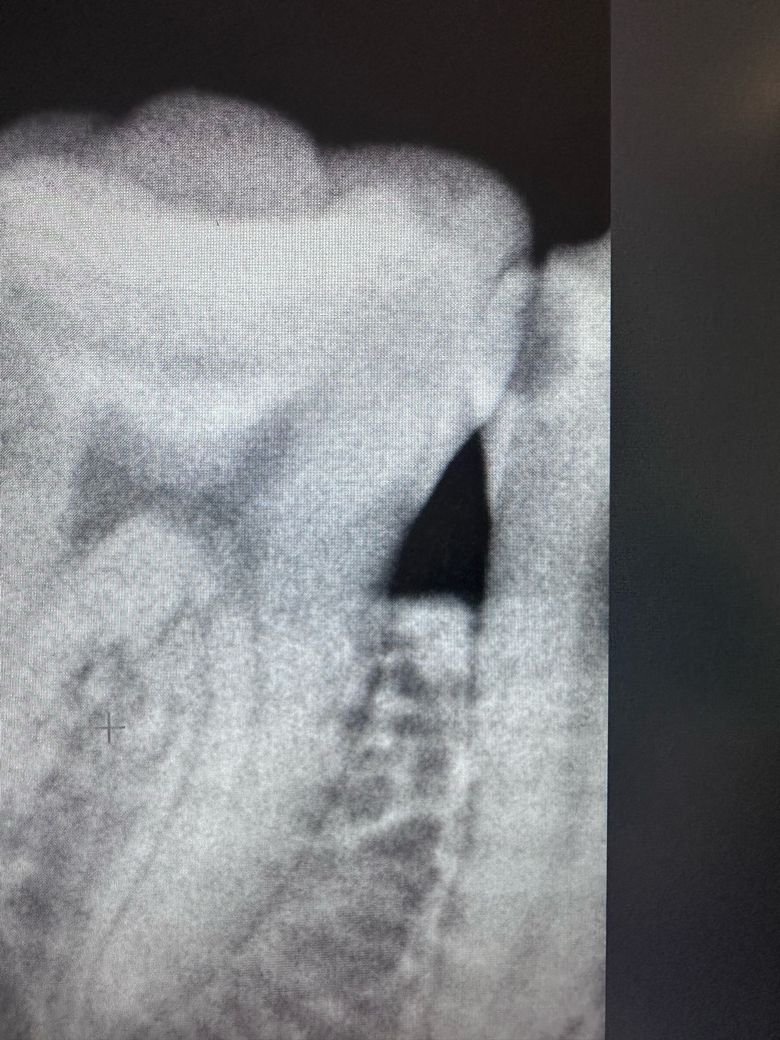

맨 3번째 사진은 작년 겨울쯤 사랑니 빼기 전 사진이에요! 저 사진에서도 충치가 보이나요??

충치가 많이 진행된거 같고 일단은 신경치료를 하지 않고 치료를 해보겟지만 신경치료 가능성이 있어 보입니다.

충치도 있고 치아도 옆면이 깨져나가서 인레이를 하자고 한것이고 여기서 치료하다가 신경이 노출되면 신경치료를 해야합니다